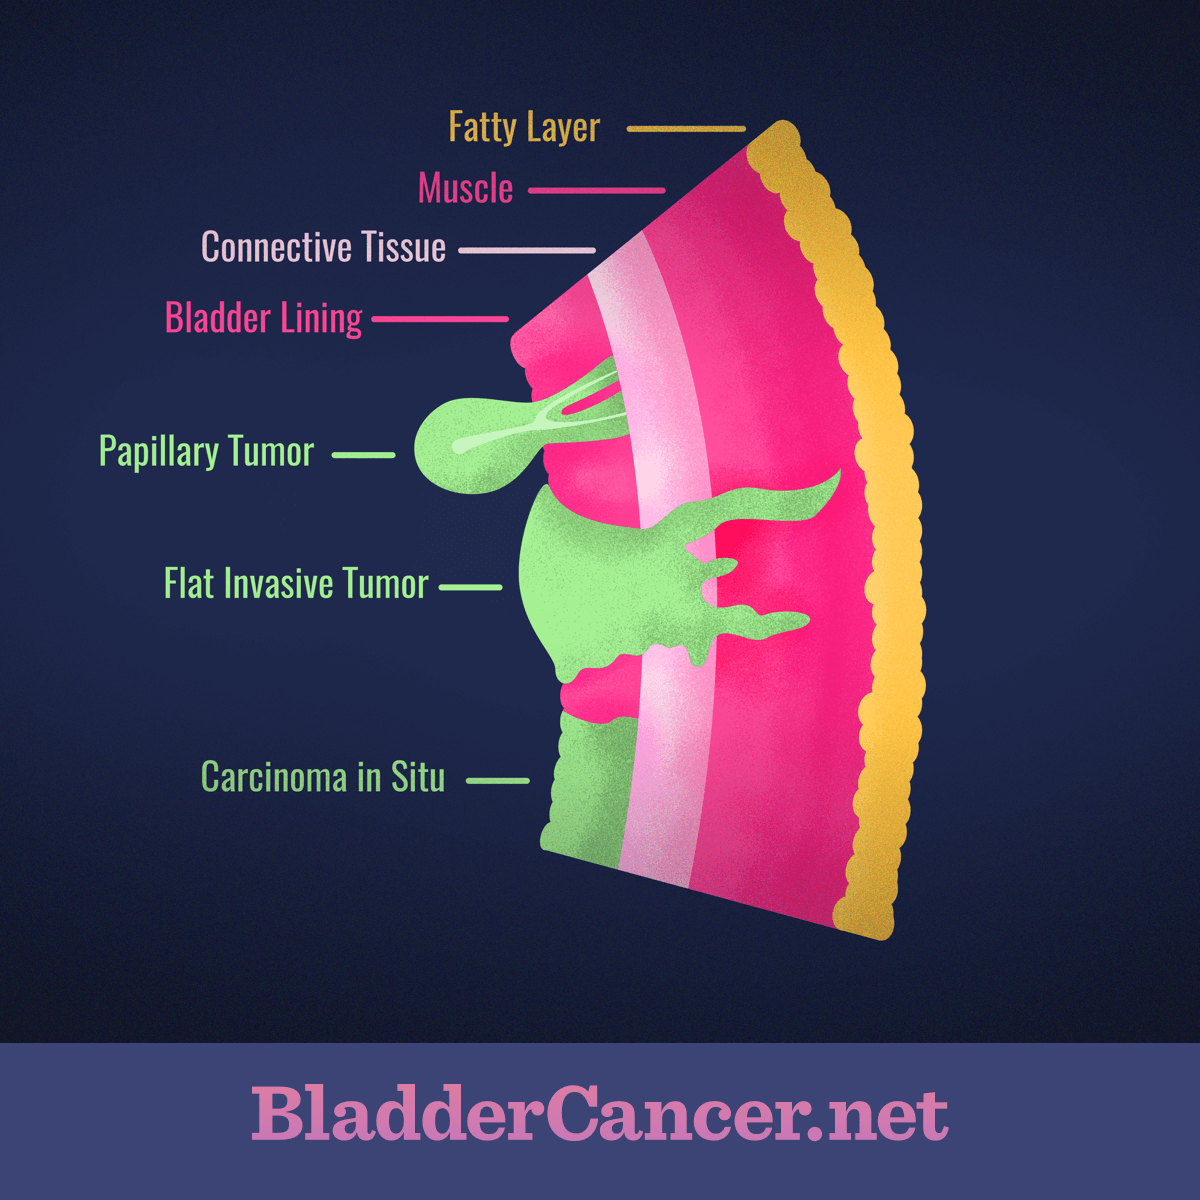

Classification Of Bladder Tumors : TNM stage classification of bladder …

Understanding the Different Types and Forms of Bladder Cancer

Stages of bladder cancer from Meyer et al., (2002). Bladder cancer can …

Imaging modalities for improved bladder tumor detection. Papillary and …

Neoplasms of the Urinary Bladder: Radiologic-Pathologic Correlation …

Overview of staging and grading of bladder cancer tumor. The figure was …

Classification Of Bladder Tumors : TNM stage classification of bladder …

Update on Bladder Cancer for the Practicing Pathologist

Imaging modalities for improved bladder tumor detection. Papillary and …

Bladder Cancer Pathology – Net Health Book

Tumors of the Bladder: Cystoscopic and Radiographic Appearance